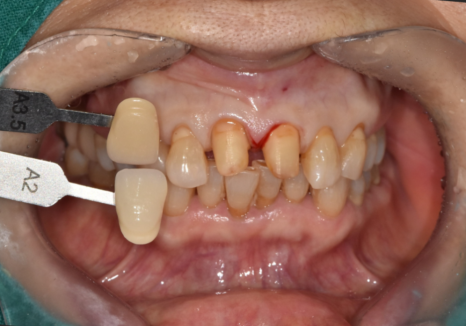

그런데 사실 앞니 치료를 할 때 환자분들이

가장 걱정하시는 것 중 하나가 바로 색상입니다.

공들여 치료했는데

막상 새로 한 치아만 혼자 너무

하얗거나 튀어 보일까 봐 불안해하시거든요.

이런 고민을 덜어드리기 위해

저희는 치과 안에 기공소를 직접 운영하고 있습니다.

보통 외부 업체에 맡기면

소통 과정에서 미세한 톤 차이가 생길 수 있지만

원내 기공소에서는

제가 기공사분과 실시간으로 소통하며

환자분 고유의 치아

색상과 투명도를 정밀하게 맞출 수 있죠.

심지어 환자분이 체어에 앉아 계신 상태에서

직접 색상을 대조하며 수정하는

세밀한 작업도 가능합니다.

251229 (전) 260114(후)

이번 환자분 역시 옆 치아와 이질감이

전혀 느껴지지 않도록

자연스러운 지르코니아로 완성해 드렸습니다.^^